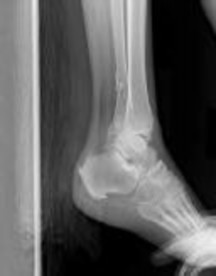

Figures 1 and 2 are the radiographs of a 68-year-old woman who comes to the emergency department after stepping into a hole and twisting her ankle. She is complaining of isolated ankle pain and is unable to bear weight.

After closed manipulative reduction and splint placement, she is scheduled for operative treatment. The stability of the syndesmosis should be evaluated after

How is syndesmotic instability best assessed intra-operatively?

How is syndesmotic reduction best assessed intra-operatively?

Our understanding of malreduction of the syndesmosis has changed over the years based on changes in technique and imaging. Our current understanding is that malreduction of the syndesmosis

Anatomic reduction and stabilization of the posterior malleolus fracture component

What is the morphology of the posterior malleolar fracture component?